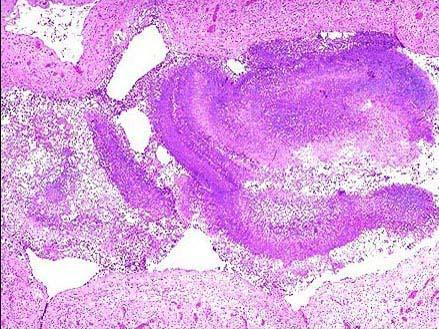

问题 糖尿病患者,男,56岁,反复刺激性咳嗽,咳棕黄色痰半年,纤支镜取活检,镜下如图所示,正确的诊断是 ( )

选项 A.肺念珠菌病 B.硅肺 C.石棉肺 D.肺放线菌病 E.肺曲菌病

答案 E